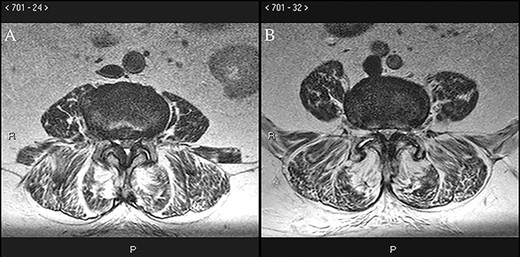

On exam, she exhibited weakness in her right iliopsoas, quadriceps, anterior tibialis and extensor hallucis longus muscle groups with pathologic hyperreflexia and markedly increased right lower extremity tone. Noncontrast lumbar spine MRI revealed L4–L5 anterolisthesis and a previously undiagnosed tethered cord with her conus medullaris extending to the L5–S1 level (Fig. 1), in addition to L3–L4 and L4–L5 central canal stenosis (Fig. 2A and B).

Preoperative axial T2 MRI at the L3–L4 (A) and L4–L5 (B) levels demonstrates ligamentous hypertrophy and central canal stenosis with cord compression.